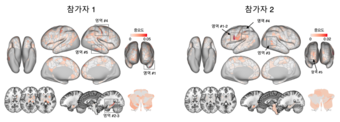

▲[그림1] 뇌 영상 기반 만성 통증 마커의 통증 세기 예측

▲[그림2] 뇌 영상 기반 만성 통증 마커의 뇌 영역별 중요도

이번 연구의 가장 중요한 발견은 통증과 관련된 뇌의 반응 패턴이 지문처럼 사람마다 다르다는 점이다. 한 환자에게서 찾아낸 통증 패턴(마커)은 다른 환자의 통증을 설명하는 데 적용되지 않았다. 이는 만성 통증이 지극히 개인적인 뇌의 반응임을 과학적으로 증명한 사례로, 각 환자의 고유한 ‘뇌 지문’을 추적함으로써 기존 공통 마커 연구보다 훨씬 높은 정확도를 달성할 수 있었다.

연구팀은 전신의 광범위한 통증이 지속되는 질환인 ‘섬유근육통’ 환자들을 대상으로 수개월간 반복하여 기능자기공명영상(fMRI)을 촬영했다. fMRI는 뇌의 혈류 변화를 감지해 어느 부위가 활성화되는지 보여주는 장치다. 연구팀은 이 방대한 뇌 영상 데이터에 인공지능(AI) 기계학습 기술을 적용하여, 개별 환자만의 고유한 ‘뇌기능 커넥톰’을 도출해냈다. 뇌기능 커넥톰이란 뇌의 여러 영역이 서로 정보를 주고받는 복잡한 상호작용 체계를 일종의 지도로 나타낸 것이다. 그 결과, 새롭게 개발된 바이오마커는 환자가 수개월 동안 겪은 통증의 세기 변화를 오직 뇌 영상 정보만으로 매우 정밀하게 예측해냈다.